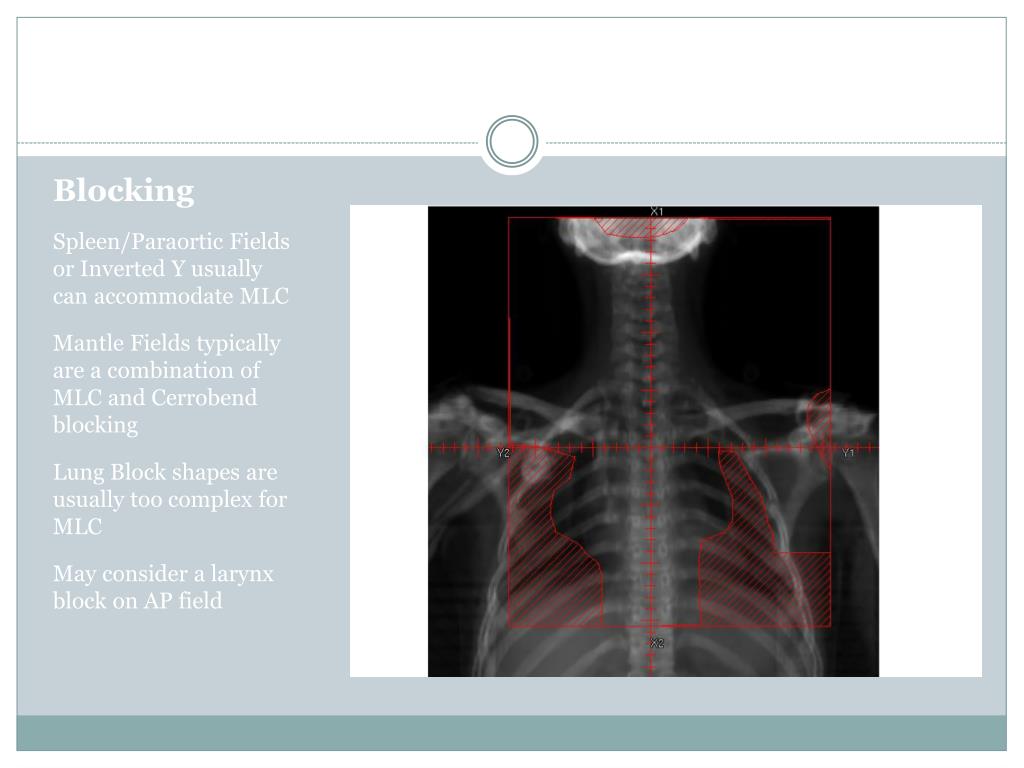

22. Blocking Spleen/Paraortic Fields or Inverted Y usually can accommodate MLC Mantle Fields typically are a combination of MLC and Cerrobend blocking Lung Block shapes are usually too complex for MLC May consider a larynx block on AP field